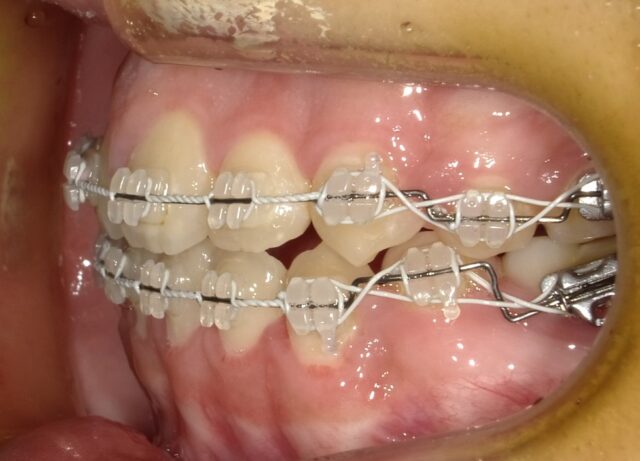

≪右側面観≫

2025年1月